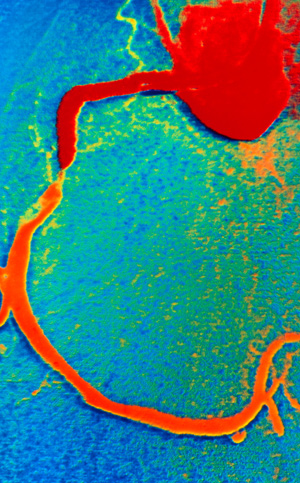

Bruk av sensitive analysemetoder for troponin hos pasienter med akutt koronarsyndrom gir bedre prediksjon av koronare stenoser ved angiografi enn tradisjonelle analysemetoder.

Ved Kardiologisk avdeling, Oslo universitetssykehus, Rikshospitalet har vi gjennomført en prospektiv studie der vi undersøkte sammenhengen mellom troponinnivåer, NT-proBNP og funn av koronare stenoser med behov for revaskularisering (1). Studien omfattet 458 pasienter henvist til koronar angiografi pga. mistenkt akutt koronarsyndrom. Vi sammenliknet den prediktive verdien av troponin T-nivåer målt ved standard og høysensitiv analysemetode og troponin I-nivåer målt med tre ulike sensitive metoder, samt av NT-proBNP-nivåer. Pasientene ble fulgt i over 3,5 år med tanke på kliniske hendelser.

Studien viser at troponinnivåer målt med sensitive metoder bedrer prediksjonen av behandlingstrengende koronare stenoser hos pasienter med akutt koronarsyndrom, sammenliknet med standardmetoden. Det var minimale forskjeller mellom de sensitive analysemetodene. Jo høyere troponinnivåene var, desto større var risikoen for å ha behandlingstrengende koronare stenoser. For langtidsoverlevelse ga NT-proBNP-målinger bedre prognostisk informasjon enn troponinmålinger. Høye NT-proBNP-nivåer var en uavhengig prediktor for død, selv etter korreksjon for kliniske variabler, kreatininverdi og CRP-nivå.